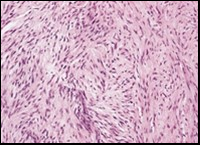

The neoplasm frequently infiltrates abutting skeletal muscle. Occasionally, tumefaction denominates hyper-cellular foci, tumour necrosis, cellular or nuclear atypia and mitotic figures, features which are characteristic of intermediate to high grade sarcoma. Localized tumour reoccurrence may be hyper-cellular with enhanced mitotic activity 4, 5. On ultrastructural examination, fibroblastic differentiation is exemplified 5. Figure 1, Figure 2, Figure 3, Figure 4, Figure 5, Figure 6, Figure 7, Figure 8.

Figure 4.Low grade fibromyxoid sarcoma composed of alternating foci of fibrous and myxoid region with interwoven fascicles and bland spindle-shaped tumour cells (12).